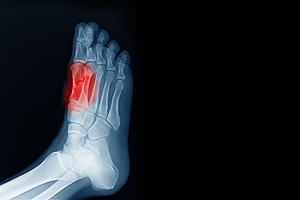

Pseudogout is a joint condition that can cause sudden pain and swelling in the feet and ankles. It occurs when calcium pyrophosphate crystals collect in the joints, leading to inflammation that can feel similar to gout. While both conditions involve crystal buildup, gout is caused by uric acid crystals and often targets the big toe, whereas pseudogout typically affects the ankle or midfoot and involves different minerals. The pain from pseudogout may come on quickly and can limit movement, making walking difficult. It tends to affect older adults, especially those with osteoarthritis or joint trauma. Diagnosis often requires imaging and lab tests to confirm the type of crystals present. Treatment for pseudogout include anti-inflammatory medication, joint aspiration, and lifestyle changes to reduce flare-ups and manage symptoms. If foot or ankle pain appears without warning and does not improve, it is suggested that you visit a podiatrist for proper evaluation and treatment.

Diagnosis of gout includes either a joint fluid test or a blood test. X-ray imaging can detect osteoarthritis but not gout. On the other hand, there is no blood test for osteoarthritis. Rheumatoid arthritis is difficult to diagnosis. Doctors utilize family and personal medical history, a physical examination, and antibody blood tests to determine if you have rheumatoid arthritis.

Gout is a form of inflammatory arthritis caused by a buildup of uric acid crystals in the joints, most commonly in the big toe. It often develops suddenly, with intense pain, redness, swelling, and warmth in the affected area. Gout attacks can last from a few days to a couple of weeks, with symptoms often peaking within 24 hours. Triggers include a diet high in purines, especially red meat, seafood, and alcohol. Other causes are dehydration, obesity, and certain medical conditions. The pain can be sharp, throbbing, and severe enough to make even light pressure, like a bedsheet, feel unbearable. A podiatrist can diagnose gout with an exam, joint fluid analysis, or imaging. Treatment may involve anti-inflammatory medication, corticosteroid injections, dietary guidance, and long-term uric acid management. Preventive care is key to reducing the frequency and severity of future flare-ups. If you have developed gout, it is suggested that you schedule an appointment with a podiatrist who can help you to manage this painful condition.

Most cases of gout are easily diagnosed by a podiatrist’s assessment of the various symptoms. Defined tests can also be performed. A blood test to detect elevated levels of uric acid is often used as well as an x-ray to diagnose visible and chronic gout.